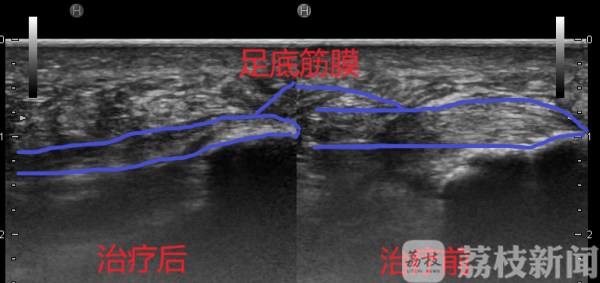

“这是足底筋膜炎导致的足跟痛,其中跖腱膜水肿已经非常明显,需要及时开展治疗。”吴野环医生表示,“足跟痛一般是由长期、慢性的损伤引起,王女士的病情很可能和暴走有关。如果不及时治疗,严重时可致足跟肿胀、发红,痛到甚至不能行走,常见足跟痛由足跟骨刺、跖腱膜炎、足跟脂肪垫炎、跟骨后滑囊炎、跟腱炎等原因引起。”吴野环医生为王女士制定了个体化的治疗方案,经过2周的治疗,王女士的足跟疼痛明显改善,决定在即将到来的“五一小长假”出门走走。